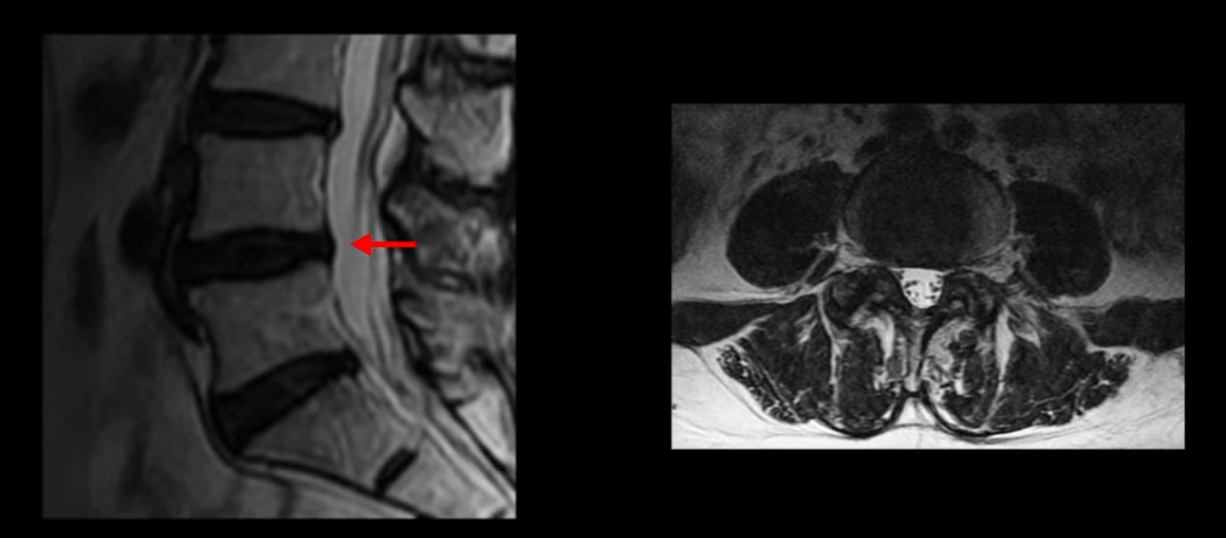

이분 MRI를 보시면 허리 세 마디가 퇴행은 있으나

척추관도 3번 4번

4번 5번

5번 1번

전부 다 충분히 넓고 왼쪽 다리 쪽으로 신경이 나가는 추간공도 전부 다 충분히 넓은 상태입니다.

신경이 눌려 보이지 않는 겁니다. 그러니까 수술 후 MRI를 보고 모든 병원이 전부 다 ‘수술은 잘돼 있다’, ‘아무것도 해줄 게 없다’ 그냥 기다리라고만 얘기했다고 합니다. 신경외과, 정형외과, 재활의학과가 서로 다른 과로 전과시키면서 다들 아무것도 해줄 게 없다고 하니 희망을 잃은 상태였다고 했습니다.